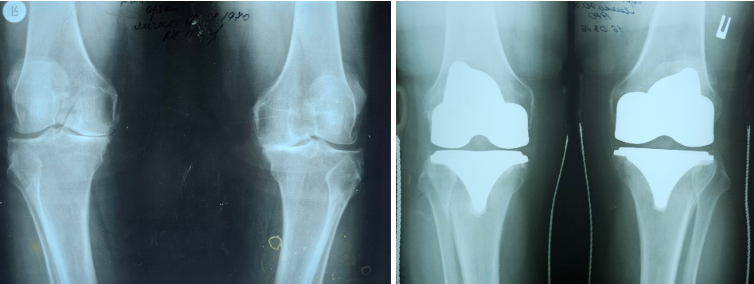

Медики відділення ортопедії та травматооогії Закарпатської обласної клінічної лікарні імені Андрія Новака виконали ендопротезування обох колінних суглобів військовослужбовцю. Оперативне втручання провели за державною програмою.

Юрію – 55 років, він служить сапером в одному з підрозділів з початку повномасштабного вторгнення РФ. За словами захисника, через надмірне навантаження під час виконання бойових завдань, з часом почали турбувати інтенсивні болі в обох колінних суглобах, з’явилася їх деформація та різке обмеження рухів.

До Закарпатської обласної клінічної лікарні пацієнта госпіталізували з діагонозом «Двобічний гонартроз IV ступеня з варусною деформацією обох колінних суглобів, стійким больовим синдромоммом та згинально- розгинальною контрактурою середнього ступеню».

«Хворому провели тотальне цементне ендопротезування лівого і правого колінних суглобів. Післяопераційні періоди проходили без ускладнень. У задовільному стані пацієнта виписали в реабілітаційне відділення ЗОКЛ ім. А.Новака, де він пройшов курс повноцінного відновно-реабілітаційного лікування», – розповів Іван Дорогій.